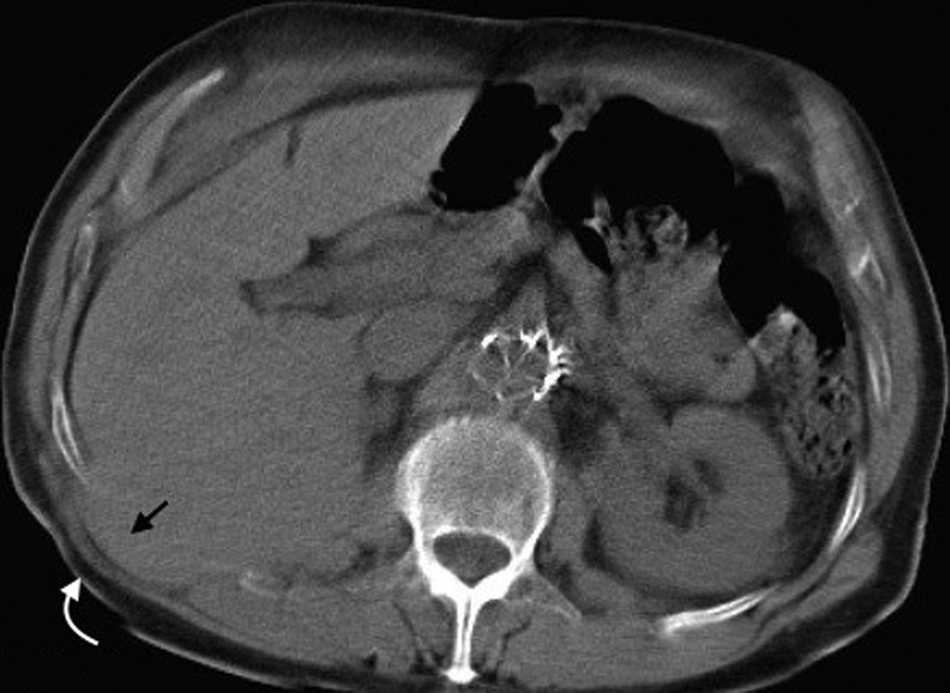

Su diagn??stico espec??fico se puede hacer si en la TCMD de pelvis se visualiza el intestino herniado entre los m??sculos pect??neo y obturador externo con obstrucci??n del intestino delgado sin una causa aparente3 (fig. 4).

El contenido est?? relacionado con los diferentes sitios de debilidad de la pared. A nivel epig??strico se encuentra una herniaci??n del antro g??strico, del l??bulo hep??tico izquierdo (fig. 14) o de la ves??cula biliar (fig. 15). Por su parte, dentro de las umbilicales puede haber grasa peritoneal, asas intestinales, implantes metast??sicos (n??dulo de la hermana Mar??a Jos??) (fig. 16) o l??quido asc??tico (fig. 17). En la hernia de Spiegel suele visualizarse grasa y asas intestinales, mientras que las obturatrices muchas veces son descubiertas porque el paciente presenta un cuadro de obstrucci??n intestinal mec??nica que ayuda al diagn??stico. En cuanto a la lumbar, se puede herniar grasa, el polo renal o el l??bulo hep??tico derecho (fig. 18). En el caso de la inguinal, esta tiene un contenido muy variado, aunque la grasa peritoneal y las asas son los m??s frecuentes (fig. 19). Adem??s, puede herniar ??rganos intrapelvianos, como la vejiga (cistocele) (fig. 20) o el ap??ndice (hernia de Amyand)20 (fig. 21), y si se produce la herniaci??n del ap??ndice dentro del canal crural, se denomina hernia De Garengeot9 (fig. 22). Finalmente, en las eventraciones se observan asas de intestino delgado y grueso, ri??ones trasplantados (fig. 23) y vejigas (fig. 24).